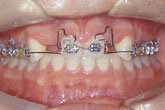

Ⅲ. 치료경과

구치부 교합은 변화를 원하지 않는 경우이므로 구치부 passive bracketing개념의 indirect bonding으로 bracket을 부착하고, 가는 wire를 사용하여 alignment를 시작하였다 (그림 6A). 016×022 Elgiloy가 들어간 상태에서 구치부에 교정용 임플란트인 screw를 매식하고 이를 anchor로 하여 좌우 견치를 원심 이동시켰다(그림 6B). 이때 구치부 치아는 main arch wire를 통하여 견치의 tipping을 막아주는 역할만 함으로, 눈에 띄는 근원심이동이나 교합변화가 나타나지 않는 것을 볼 수 있다(그림 6C). 양 중절치의 intrusion과 약간의 retraction을 위해 combination arch wire를 적용하였으며, 결손치 부위의 공간이 확보되는대로 임플란트 fixture(Frialit, 3.75mm)를 매식하였다 (그림 6D,E).

그림 6. 증례환자의 교정치료 과정